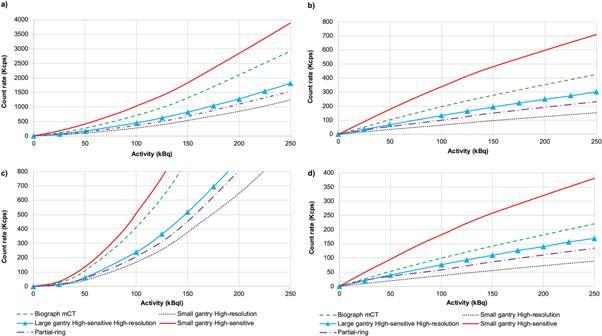

Figure 4 depicts the plots of prompt, true, random, and scatter counts for the different configurations. Figure 5 shows the NECR carve for the different configurations, supporting the results obtained for the sensitivity.

Figure 4. Plots of count rates showing: (a) prompts, (b) trues, (c) randoms, (d) scatter for the simulated configurations of PET scanners compared with the Biograph mCT.